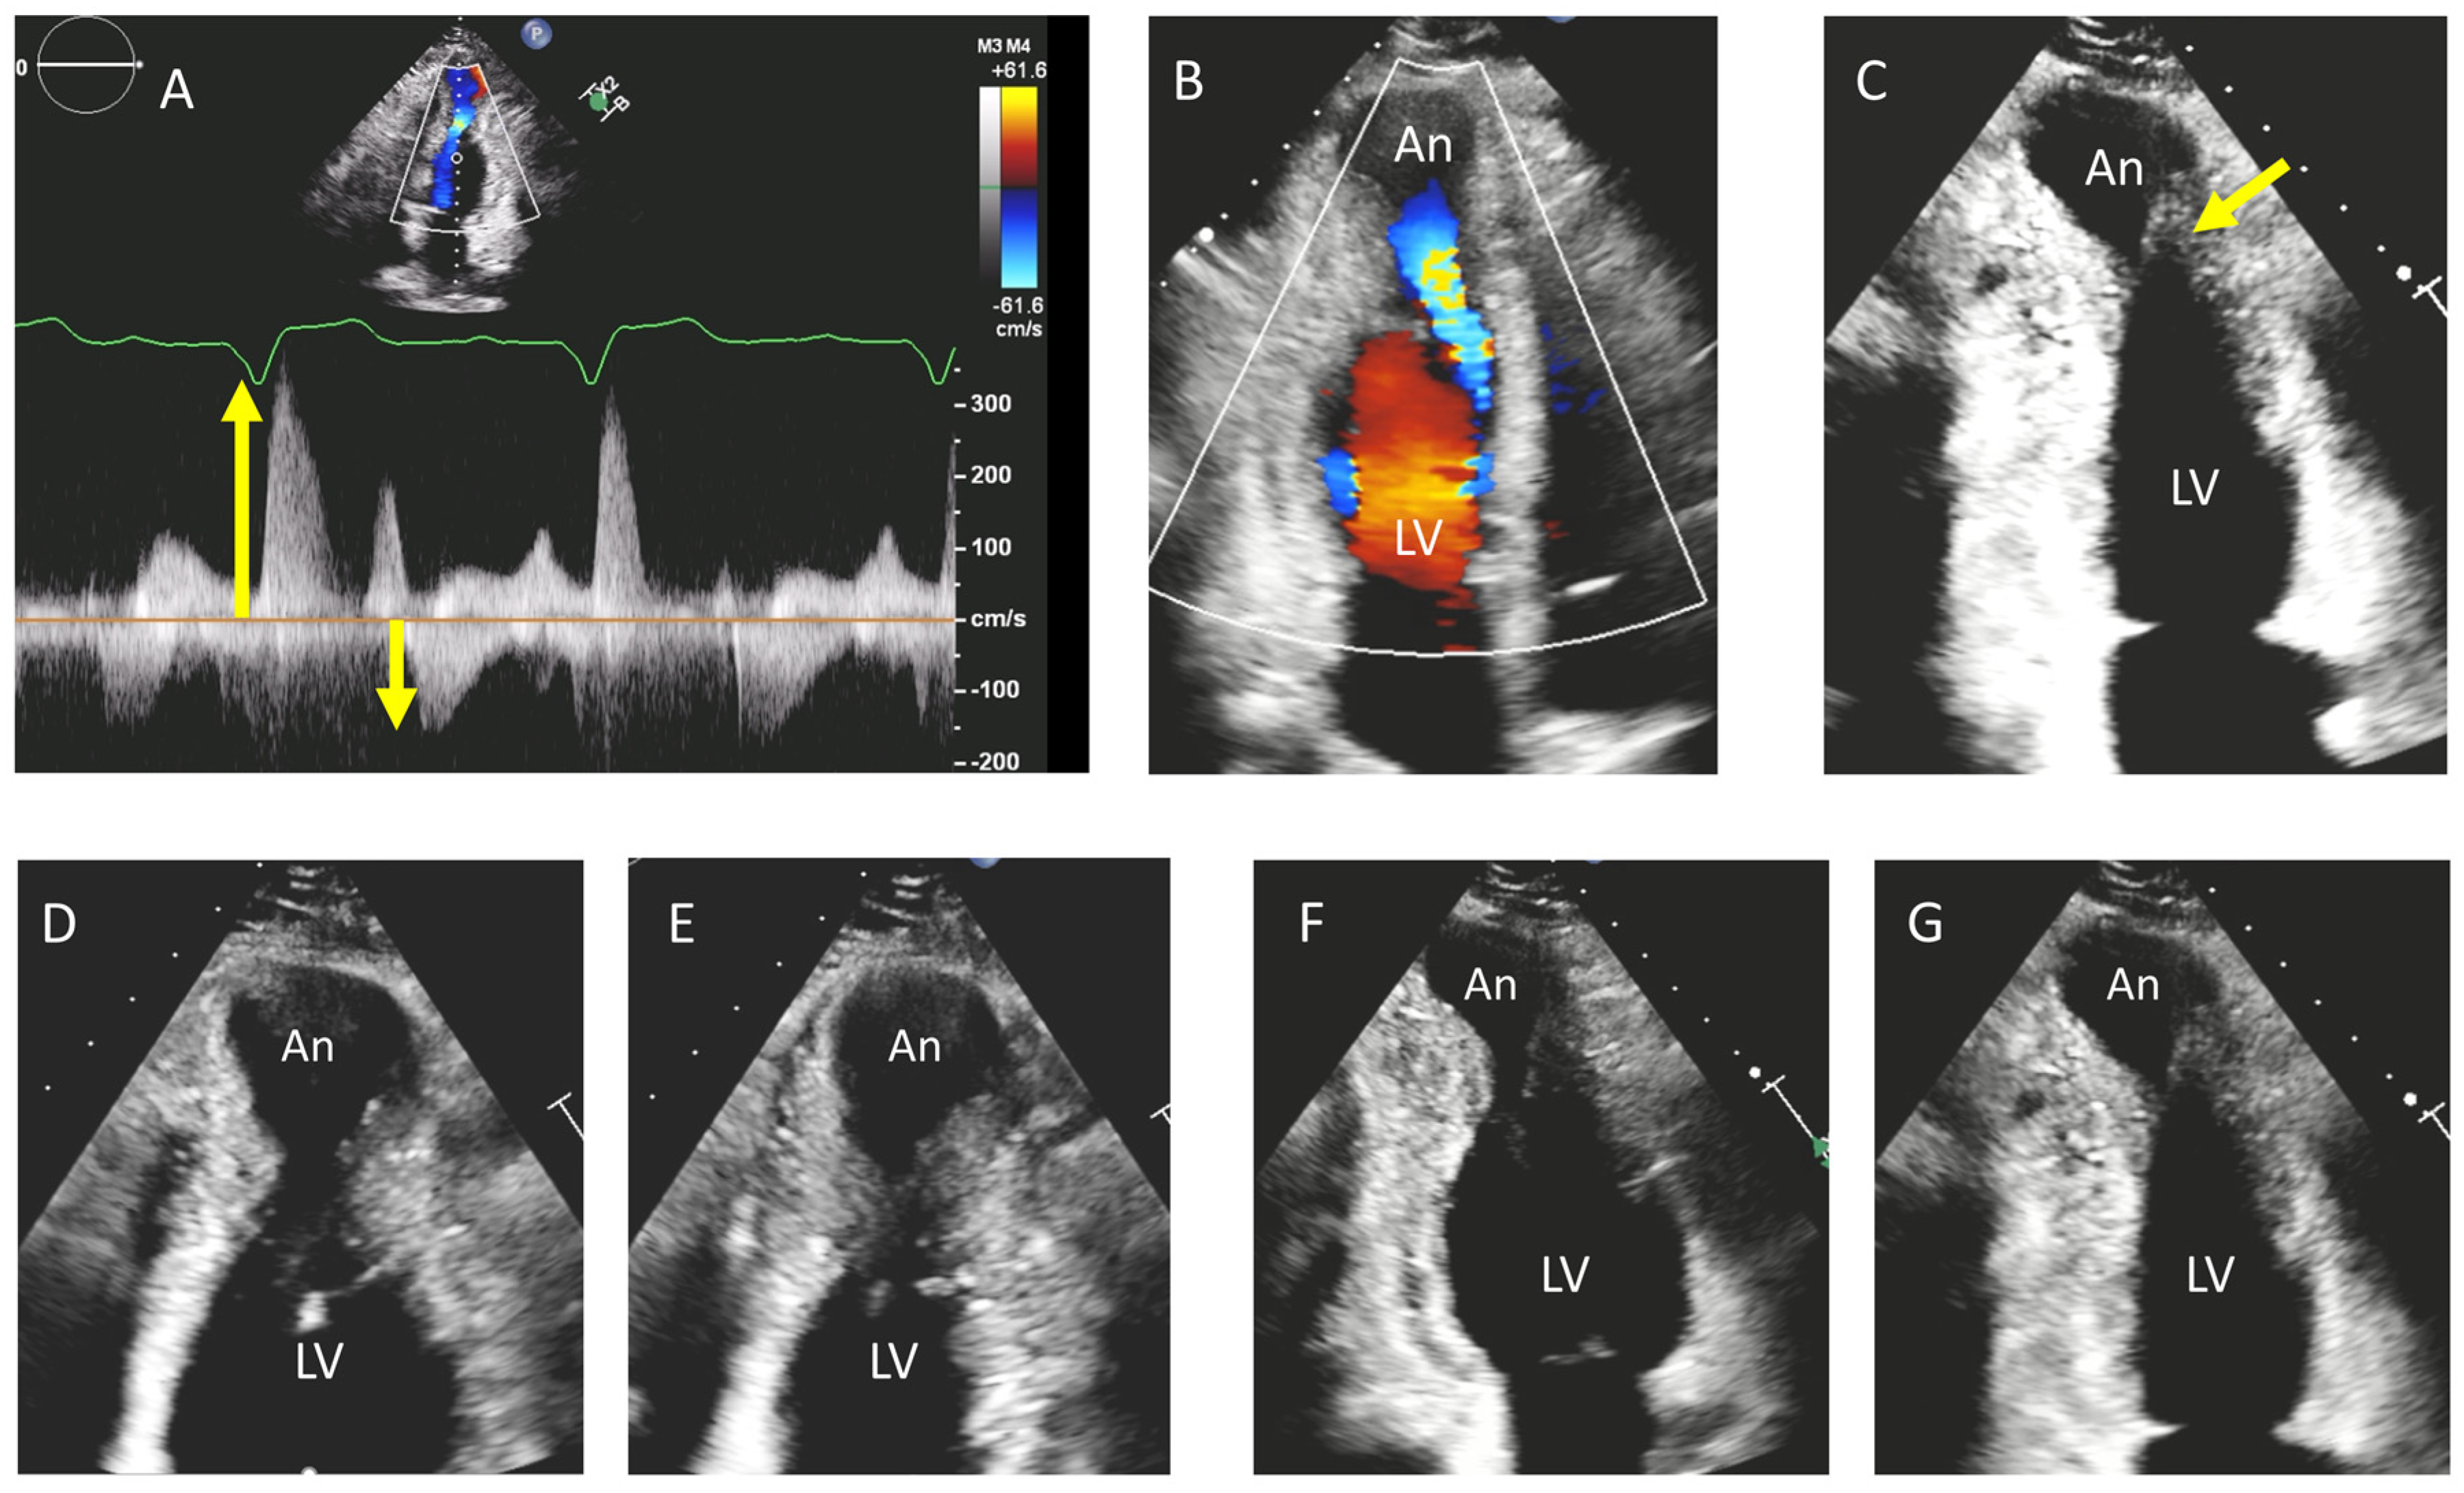

3. Apical Hypertrophy (With or Without Aneurysm)

- Lo Russo, G.V.; Pepi, M.; Mushtaq, S.; Mantegazza, V.; Celeste, F. Is There a Typical Doppler Pattern in Patients With Apical Hypertrophic Cardiomyopathy With Aneurysm? JACC Case Rep. 2023, 14, 101836. [Google Scholar] [CrossRef]

| Echocardiography | Septal hypertrophy; LVOT obstruction; SAM of the anterior mitral leaflet ± SAM-associated mitral regurgitation | Uniform thickening of LV walls; no LVOT obstruction typically | Apical wall thickening; “ace-of-spades” morphology of the LV cavity; ±apical aneurysm |

| Hemodynamics | Dynamic LVOT obstruction present in the obstructive form; diastolic dysfunction; mid-ventricular obstruction may be present | Diastolic dysfunction; usually no LVOT obstruction. | Diastolic dysfunction; no LVOT obstruction; mid-ventricular obstruction frequent |

| CMR Findings | Asymmetric septal hypertrophy; LGE at RV insertion points and patchy LGE at the site of maximum hypertrophy | Symmetrical hypertrophy with variable patterns of LGE | Apical cavity systolic obliteration, loss of apical tapering; an apical aneurysm ± apical LGE and/or thrombus may be present |